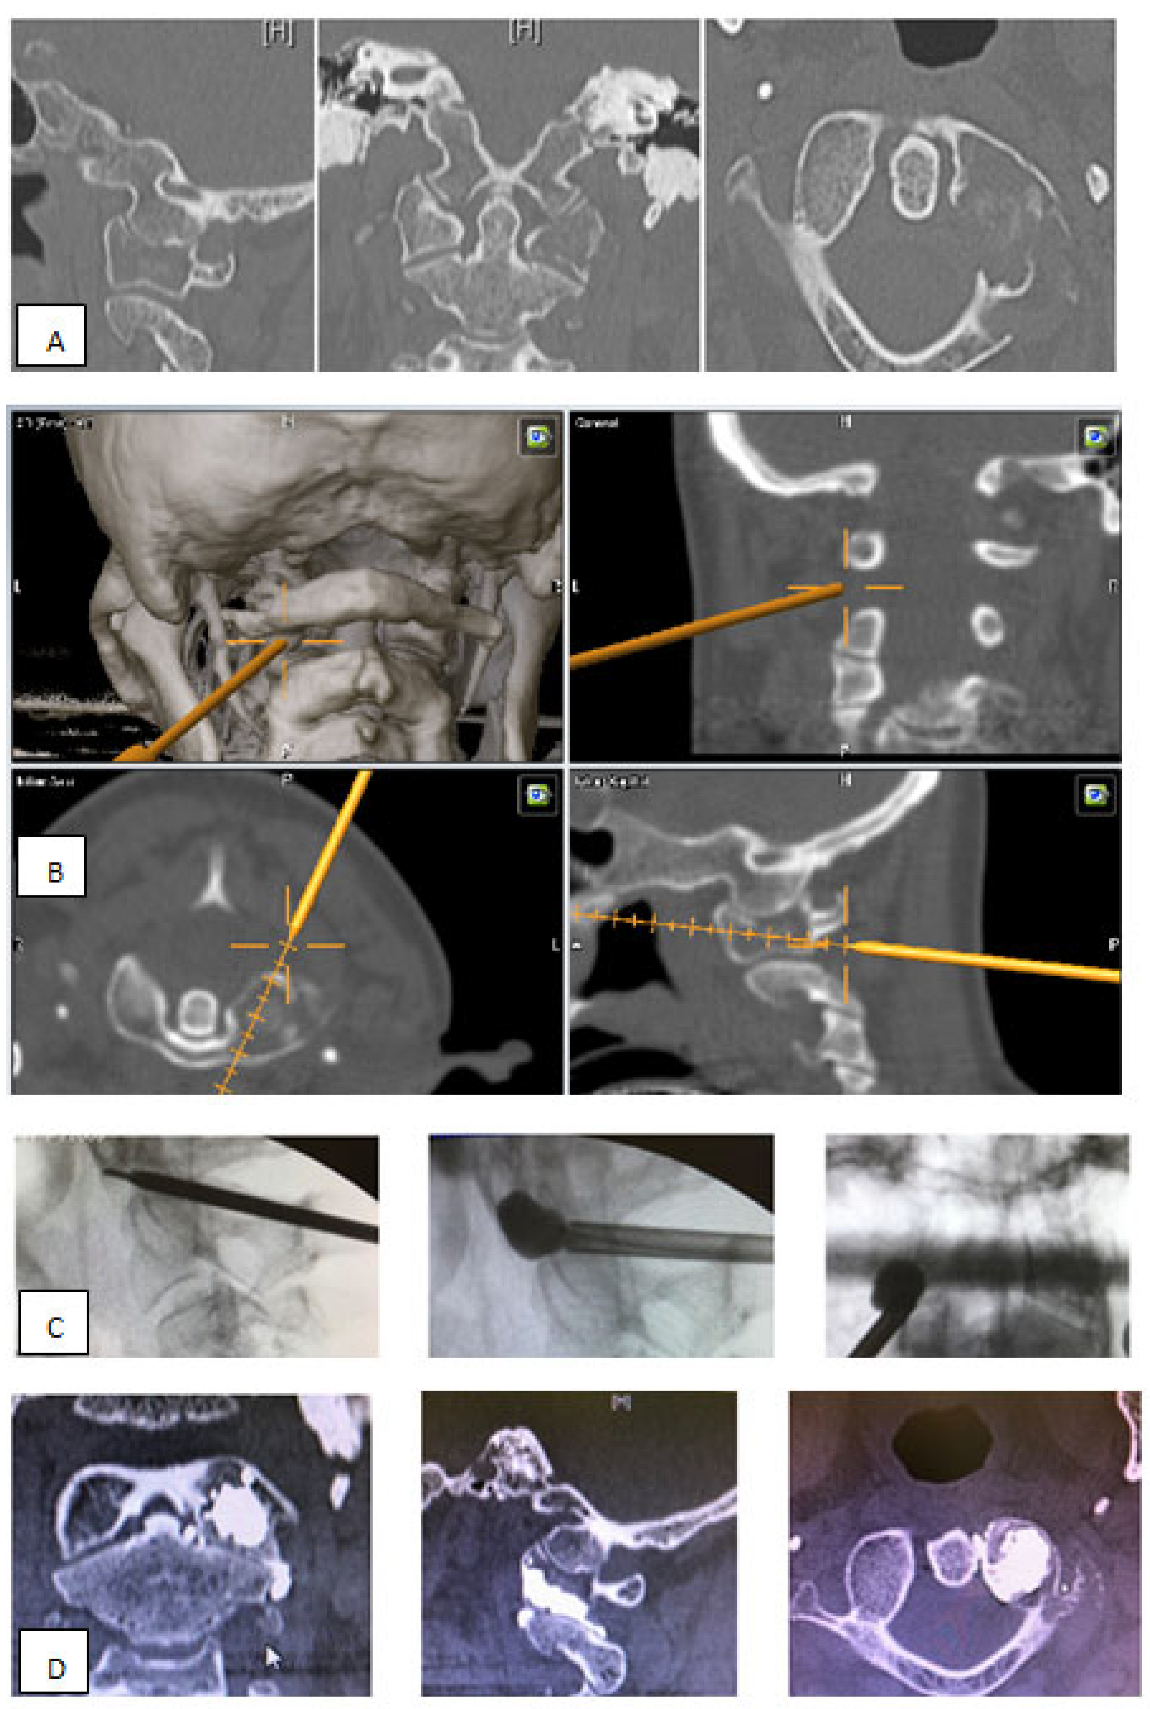

- Metastatic lesions of C1 are extremely rare, and their treatment by percutaneous cement augmentation is considered to be a technically challenging procedure due to complex anatomy. We also performed percutaneous kyphoplasty in a painful osteolytic lesion located on the left lateral mass of C1 through a posterolateral approach using a 3D CT scan intra-operative navigation system and fluoroscopy (Figure 3) [22].